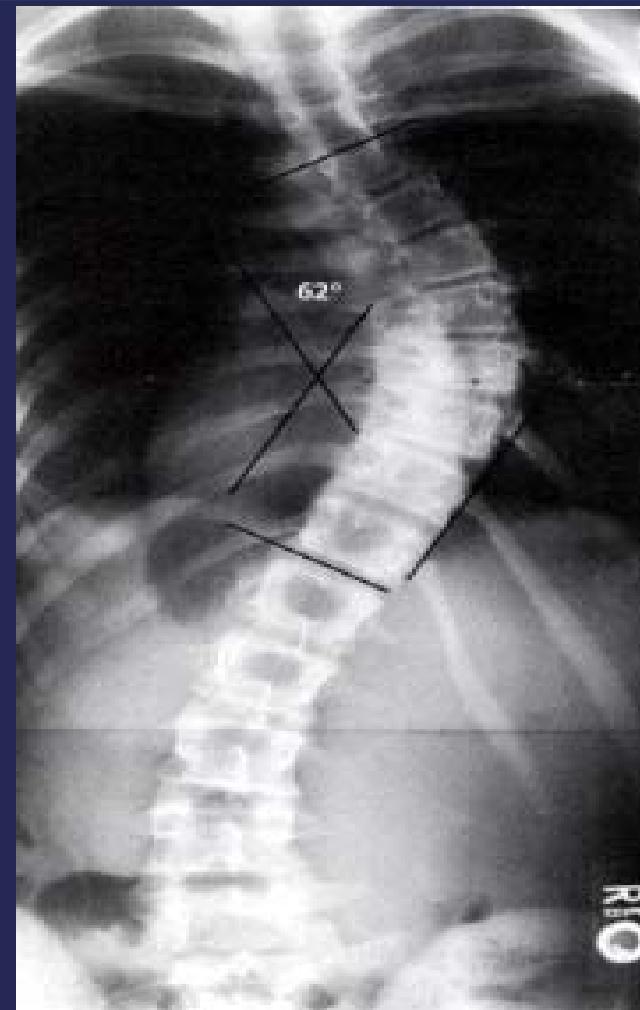

Cobb’s Angle

- Measures the amount of curve

- Angle between perpendicular lines to the uppermost and lowermost vertebral bodies in the curve

Cobb Angle Measurement

- Select most tilted vertebrae above and below curve apex

- Angle between intersecting lines drawn perpendicular to superior vertebra top and inferior vertebra bottom